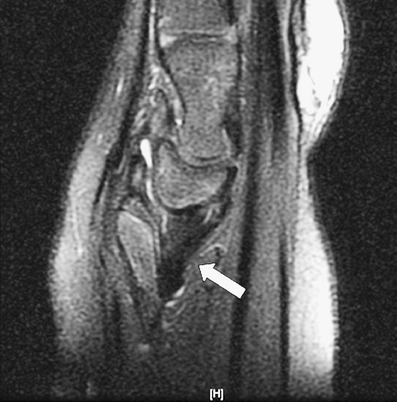

An 11-year-old girl with chronic left wrist deformity and pain underwent MRI evaluation. Coronal intermediate-weighted sequence with fat suppression showed a triangular deformity with medial tilt of the distal radius and proximal migration of the triangular-shaped lunate (Fig. 1). The triangular fibrocartilage complex (TFCC) demonstrated diffuse thickening and oblique orientation (Fig. 1, arrow). These findings are suggestive of Madelung deformity. Sagittal intermediate-weighted sequence with fat suppression showed diffuse thickening of the radiolunate ligament, suggesting Vickers ligament (Fig. 2).

Fig. 2

Sagittal image